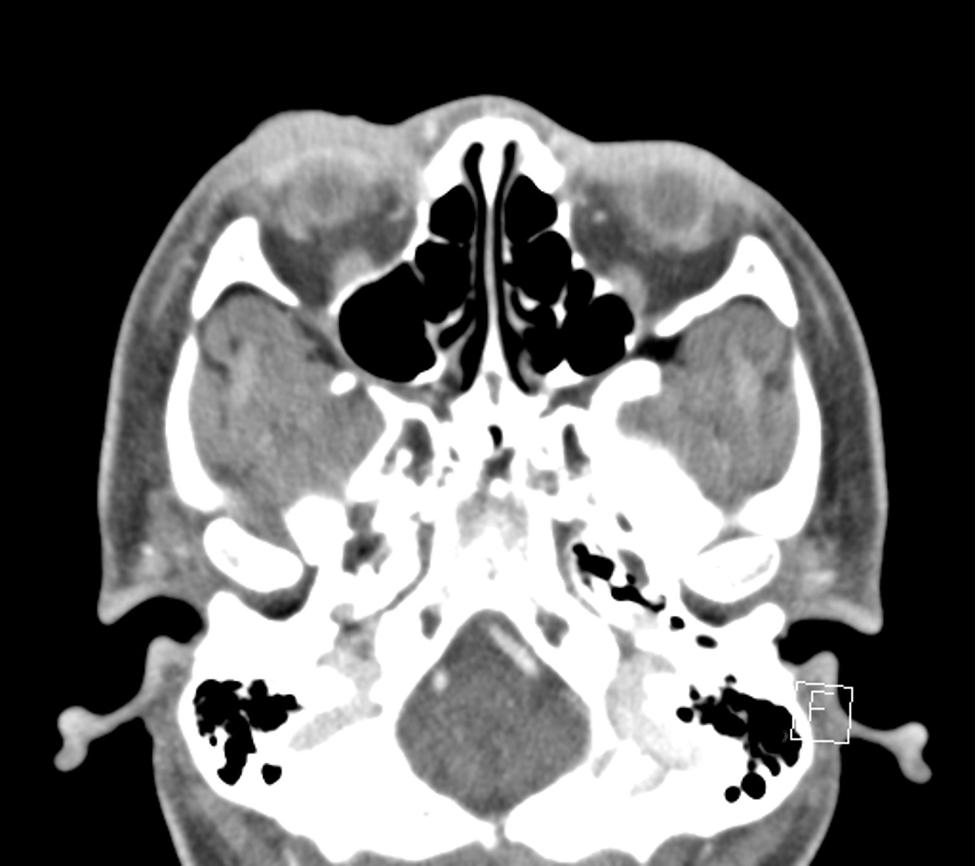

Intraorbital Foreign Body A patient presented with right eye redness, swelling, and diplopia for 6 weeks after a dirt bike accident, where his right eye hit a tree branch. He underwent imaging and evaluation at an outside institution which revealed orbital fractures, but no evidence of an orbital f…